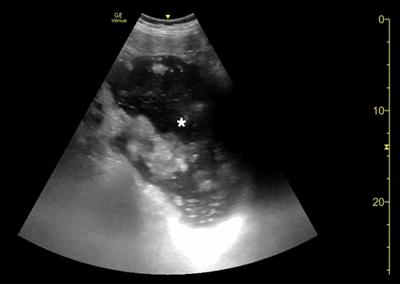

腹部床旁超声检查(POCUS)显示,胃部扩张并充满液体,高度疑似梗阻(图1,2)。

(图2)

当怀疑有胃扭转时,选择初始的影像学检查非常重要,因为诊断延迟可能导致致命的并发症。CT检查高度可靠,主要有两种表现,即正常的胃窦幽门移行区和胃窦位置异常,诊断急性胃扭转的敏感性和特异性均为100%。POCUS是一种有效的非侵入性影像检查方式,主要用于床旁评估。此外,POCUS无辐射,并可根据临床情况随时进行重复检查。本例患者POCUS检查显示,胃部严重扩张,胃内容物分层,类似胃出口梗阻(GOO)的“黑白饼干”征象。POCUS还可以用来动态视察胃减压成功与否。